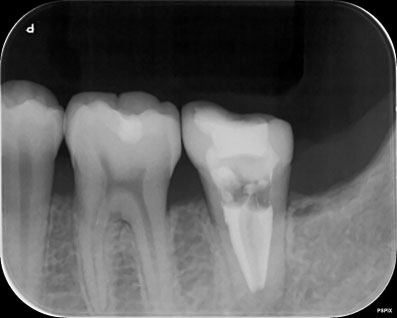

歯根の周囲には、歯根を取り巻くようなX線透過があります。(炎症があるということです)

ガッタパーチャを完全に除去し、別の薬に置き換えました。別の薬が根の先まで到達しているのがわかると思います。

根管の中には、ガッタパーチャという天然ゴムの根管充填材がありますが、これが緊密に歯根の尖端まで充填(詰め)されていないので、このような状態となっています。まずは、このガッタパーチャを完全に除去することが重要です。